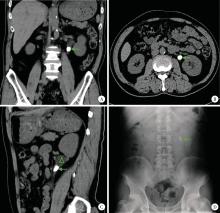

Figure 1

Imaging characteristics of urolithiasis with largest diameter ≥ 1.5 cm A, coronal CT image, with the arrow indicating the left ureteral calculus, measuring greater than 1.5 cm in length; B, axial CT image, where the arrow marks the location of the calculus; C, sagittal CT image, with the arrow identifying the calculus; notable hydronephrosis due to ureteral obstruction is observed above the calculus (indicated by the triangle); D, the kidneys, ureters, and bladders appearance of a ureteral calculus with a maximum dia-meter of ≥1.5 cm, highlighted by the arrow."